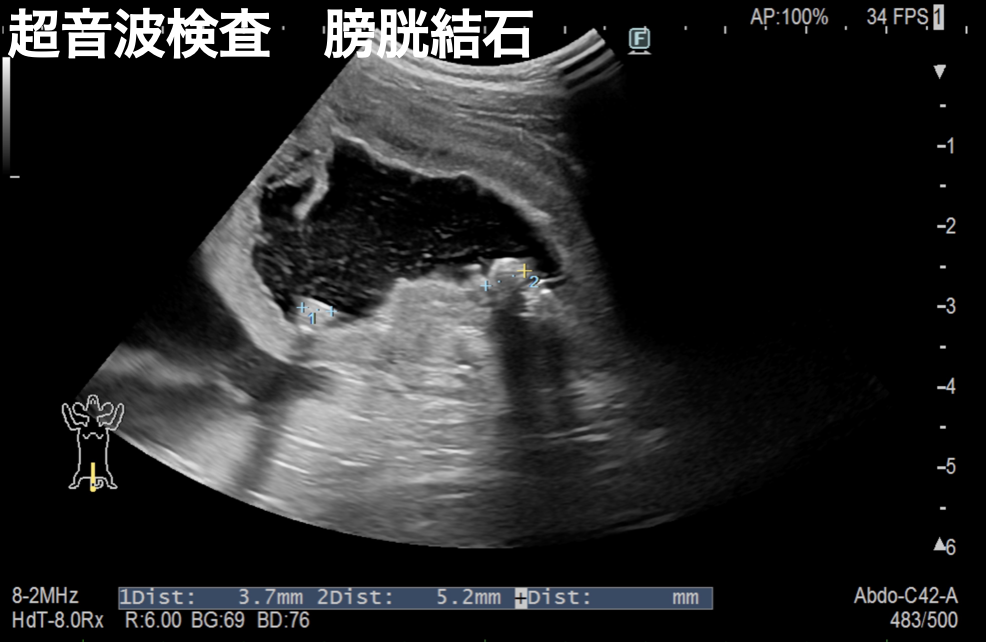

膀胱は顕著に暗赤色~赤色に変色しており、周囲組織との癒着を認めました。膀胱腹側に破裂部位を認め、 膀胱内の結石を摘出、膀胱は血流が確認される部位まで切除し縫合しました。

尿道閉塞は緊急疾患であり、閉塞が長期に続く場合には、本症例のように膀胱破裂する危険性もあります。特にダルメシアンは尿酸アンモニウム結石に罹患しやすいと報告されており、食事療法による再発防止が必要です。